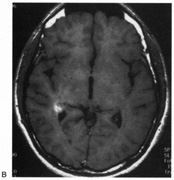

Achromatopsia in the contralateral hemifield alone can follow unilateral right or left occipital lesions (Fig. 18). Patients are typically asymptomatic until the defect is demonstrated on examination.234,235 Hemiachromatopsia is usually associated with a superior quadrantanopia;234,235,241 therefore, the color defect is only demonstrable in the remaining inferior quadrant. The preserved color vision in the ipsilateral hemifield allows normal or near-normal performance on centrally viewed tests of color vision such as pseudoisochromatic plates. The incidence of hemiachromatopsia is probably underestimated, given its asymptomatic nature and the failure of routine clinical color tests to detect its presence.

Fig. 18. Magnetic resonance imaging scan of patient with stroke causing a right hemiachromatopsia as well as partial superior quadrantanopia.